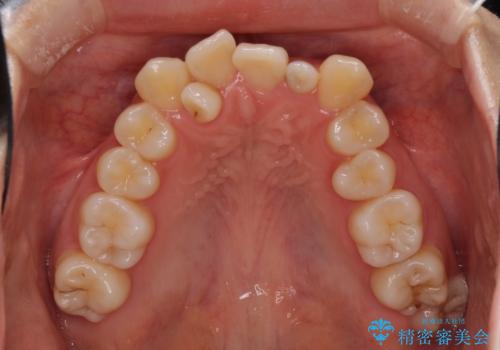

- 上顎の重なっている前歯を気にして来院された患者様です。

重なっている部分は抜歯が必要で、歯の移動量が多く、更には右側にずれている正中を改善する必要がありました。

インビザライン単体での治療は困難と判断し、補助装置により八重歯移動後にインビザラインを用いることとしました。